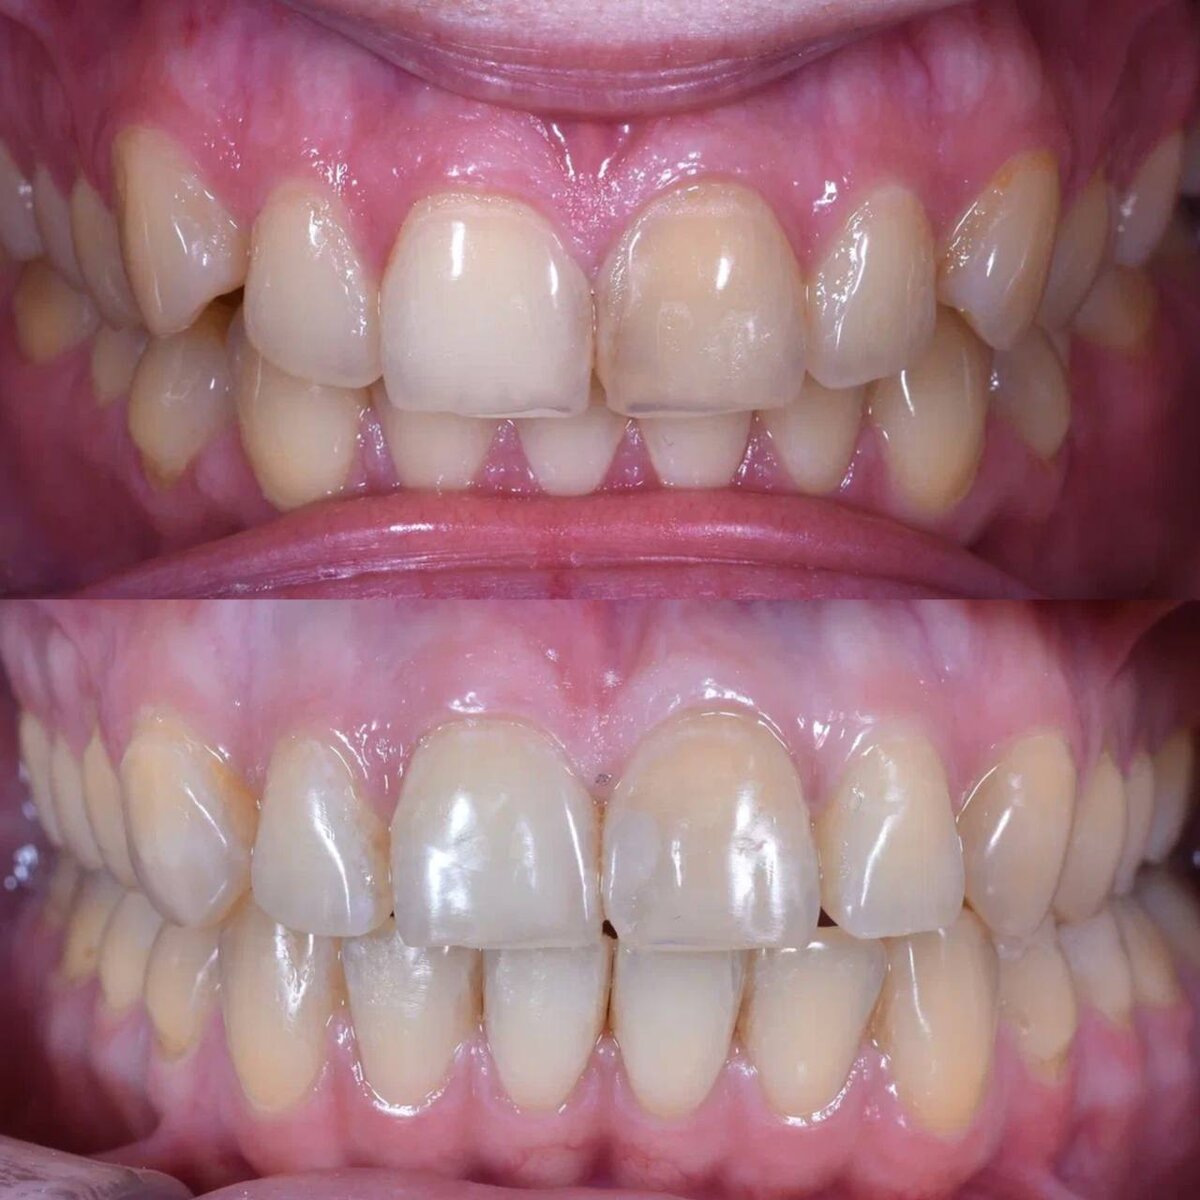

Результат лечения

Пациентка обратилась с жалобами на сильную стираемость и чувствительность зубов. Также, был выявлен неправильный прикус и сильный спазм жевательных мышц, который доставлял ей дискомфорт.

Итак, на этой фотографии мы видим ярковыраженную стираемость зубов.

Вернёмся к тому, что у пациентки была сильная стираемость зубов и для проведения качественного лечения, нам было необходимо восстановить утраченную анатомическую форму зубов с помощью керамических накладок. И на этом этапе пациентка была направлена к врачу-ортопеду.

После всех пройденных этапов лечения пациентку больше не беспокоит спазм мышц и бруксизм. Мы смогли создать красивую и здоровую улыбку, которая сохраниться на долгие годы благодаря комплексному подходу к лечению.